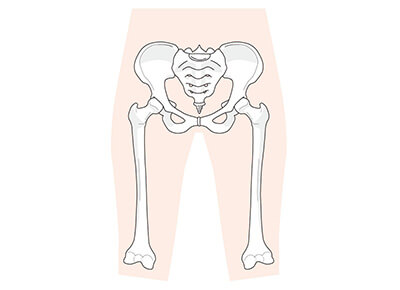

当院の骨盤調整は、骨盤そのものだけではなく、足元や背骨など全身の骨格を調整いたします。これは、骨盤のゆがみは、全身の骨格を調整することによって改善しやすくなるためです。

まずは、患者様の身体のバランスや骨格の状態をチェックし、状況を把握したうえで患者様に合った治療を施します。